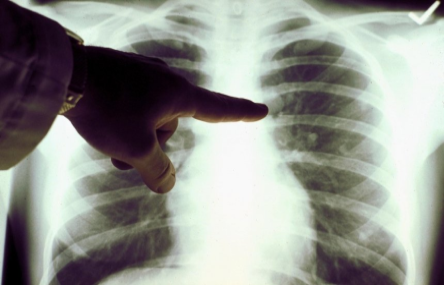

С сегодняшнего дня в Украине будут проверять на COVID-19 всех людей с пневмонией - Минздрав

В Украине с сегодняшнего дня будут проверять на коронавирус всех людей с пневмонией. Об этом на брифинге сообщил заместитель министра здравоохранения - главный санитарный врач Украины Виктор Ляшко, передает корреспондент УНН.

"С сегодняшнего дня мы тестируем всех с пневмонией, которые находятся в инфекционных больницах и больницах другого профиля, но у которых есть диагноз "пневмония", - сказал Ляшко.